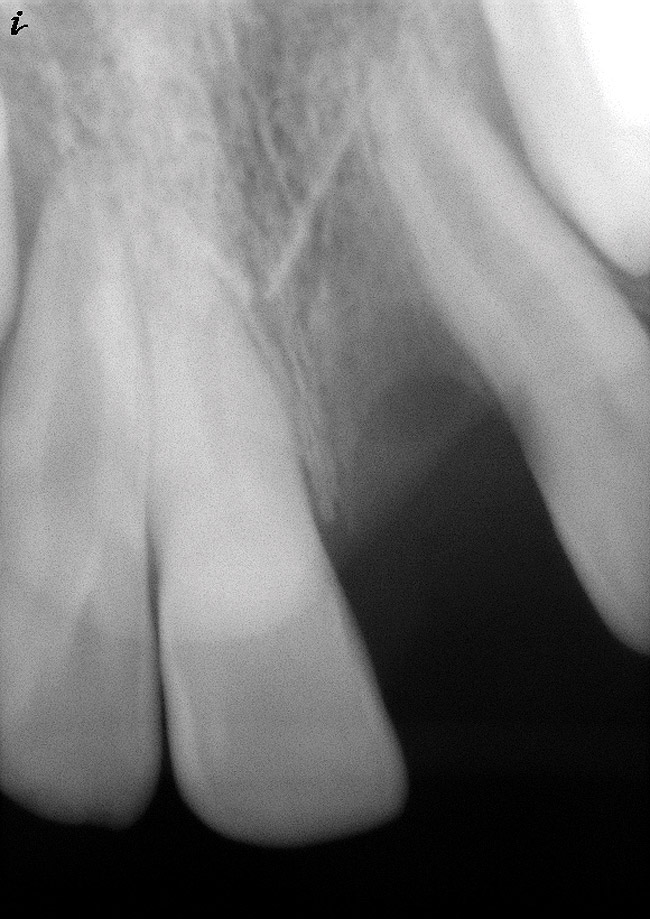

As mentioned, all risk factors associated with both root canal and implant therapy must be carefully considered. Comprehensive clinical and radiographic assessments are necessary to evaluate the patient's risk factors associated with his or her particular case (Figure 1, Figure 2 and Figure 3). The primary risk factors for implants can include smoking, bone quality, and systemic health. For endodontic therapy the primary risk factors are related to the anatomic root complexity, failed root canal treatment with significant technical defects manifested as iatrogenic events, less-than-optimal periodontal status of the tooth (due to a subsequent risk of vertical fracture), and a clinician's lack of experience with regard to the case's complexity. A strong correlation exists between failed root canal treatment and a lack of coronal seal after treatment. This is highly relevant in treatment planning. Often, endodontically treated teeth fail not because they were treated inappropriately and need extraction, but rather, because they have been left unsealed and assaulted by bacteria after the endodontic therapy, causing subsequent long-term clinical failure (Figure 4 and Figure 5).